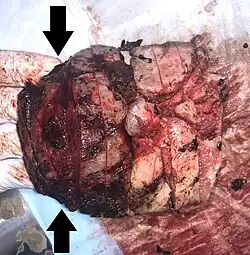

| Gross pathology of severe intervillositis, with dark red and soggy tissue. | |

Chronic Histiocytic Intervillositis (CHI or CHIV) also known as Chronic Intervillositis of Unknown (A)etiology (CIUE) and Massive Chronic Intervillositis (MCI) is defined as a diffuse infiltration of mononuclear cells (histiocytes, lymphocytes, monocytes) of maternal origin into the intervillous space within the placenta. It often results in severe intrauterine growth restriction which can lead to miscarriage or stillbirth. Overall perinatal mortality rate is high: 41%[6] to 77%.[7] Recurrence rate is also high: 67%[7] to 100%.[6]